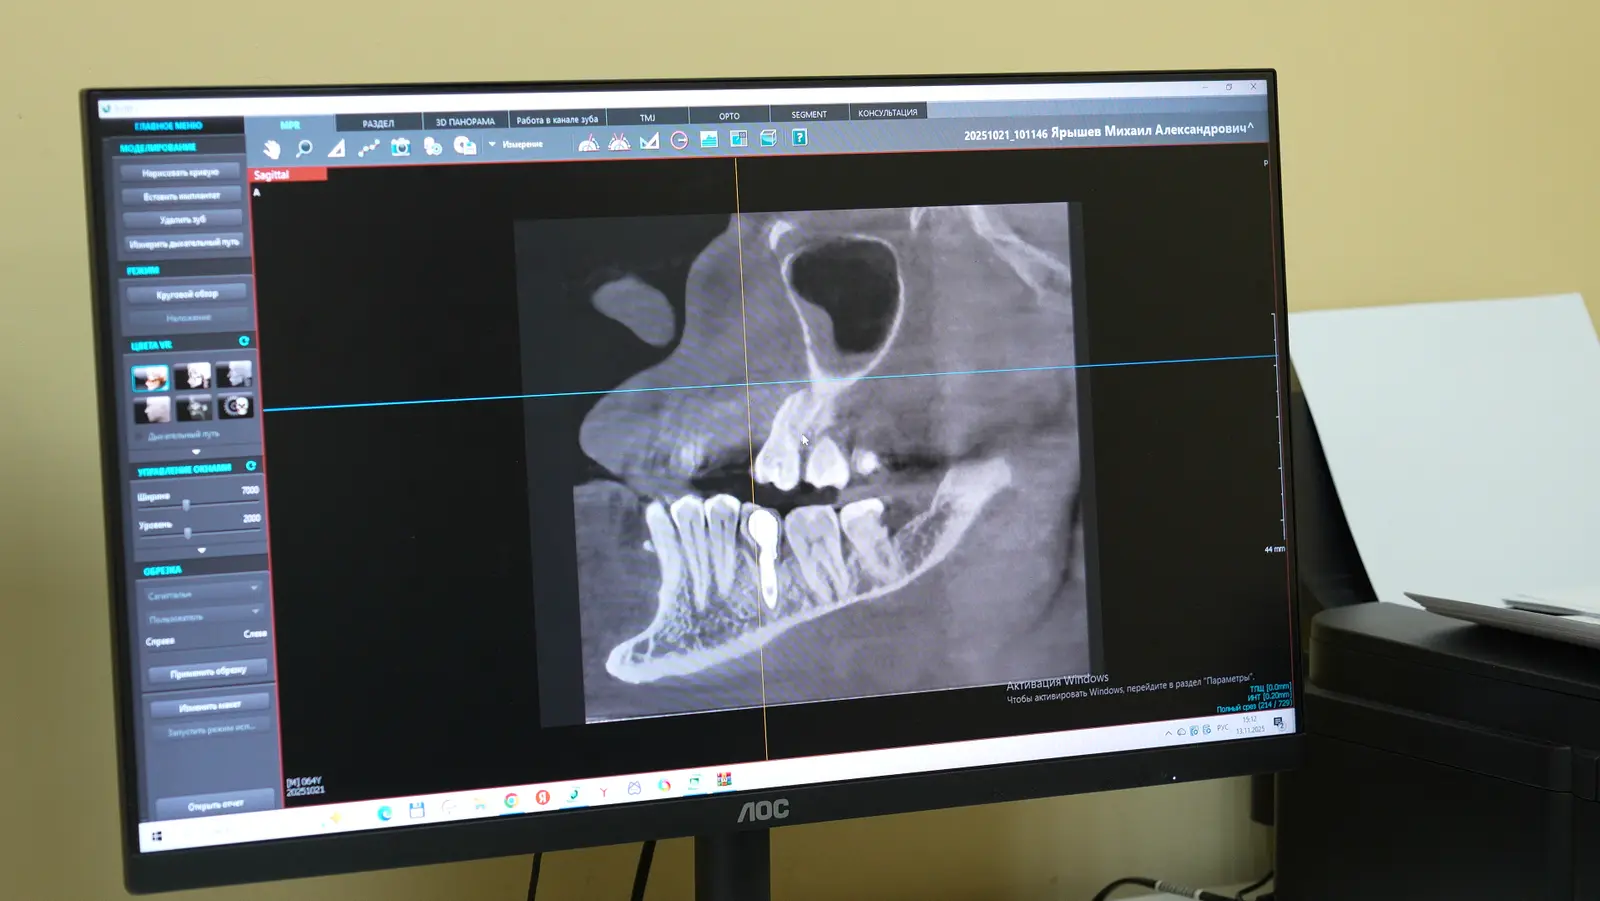

• КТ (компьютерная томография  — ключевое исследование. Оно показывает высоту, ширину и плотность костной ткани, позволяет оценить близость важных анатомических структур.

Снимок КТ